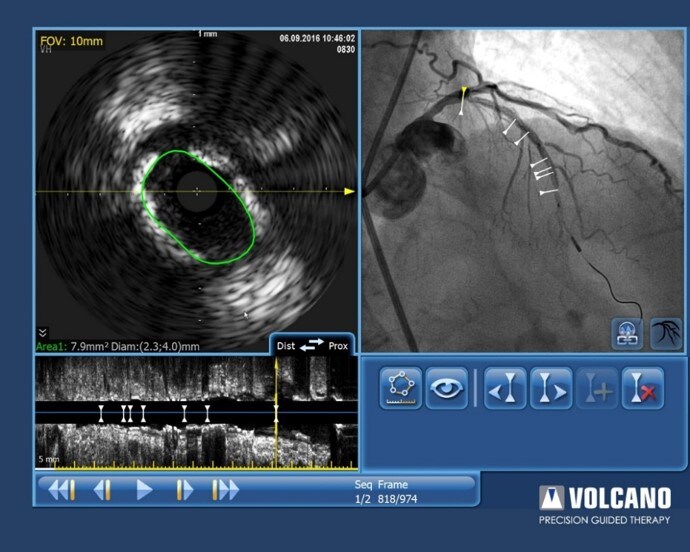

Nachdem ein Stent medial im Gefäß plaziert wurde, musste die behandelnde Person nun entscheiden, ob der proximale RIVA ebenfalls zu behandeln sei. Die Tri-Registrierung konnte dem fraglichen Segment einen iFR-Wert von 0,98 sowie eine Schnittfläche von 7.9mm² im IVUS zuordnen.